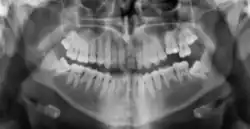

Radiographic appearance

On radiographs, enamel appears as the most radiopaque (white) structure due to its high mineral content.[19] Dentine and cementum are less radiopaque and are usually indistinguishable from each other.[19] The pulp chamber and root canals are radiolucent (dark), centrally located within the tooth structure. The periodontal ligament appears as a thin, radiolucent line between the root and the lamina dura.[19]

Figure 5: X-ray showing mixed primary and permanent teeth of an eight-year-old boy